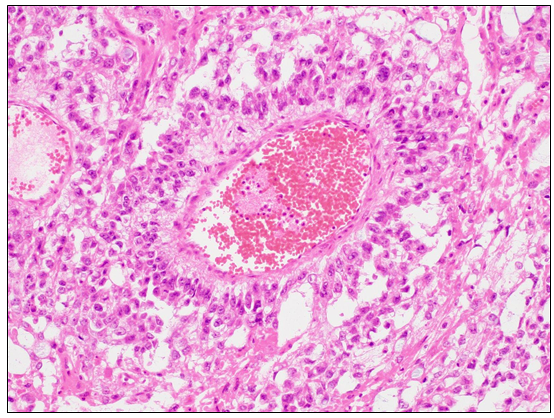

18세 여자가 2개월간 복부에 불편감이 있다며 병원에 왔다. 혈청 알파태아단백은 560 ng/mL이다. 영상검사에서 우측 난소에서 12 cm 크기의 덩이가 발견되어 우측 난소 절제술을 시행하였다. 덩이의 절단면은 매끄럽고 고형성 부분과 낭 구조가 함께 관찰되었으며 출혈이 많았다. 현미경 소견이다. 진단은?

[난황낭종양, yolk sac tumor]

• 조직학적 소견으로는 germ cell이 혈관을 층층히 감싼 구조인 Schiller-Duval body가 특징적으로 관찰된다. 또한, 난황에서 기원하는 암이기에 높은 AFP 수치가 관찰된다.

Schiller-Duval body, Wikipedia Commons (Creative Commons License)